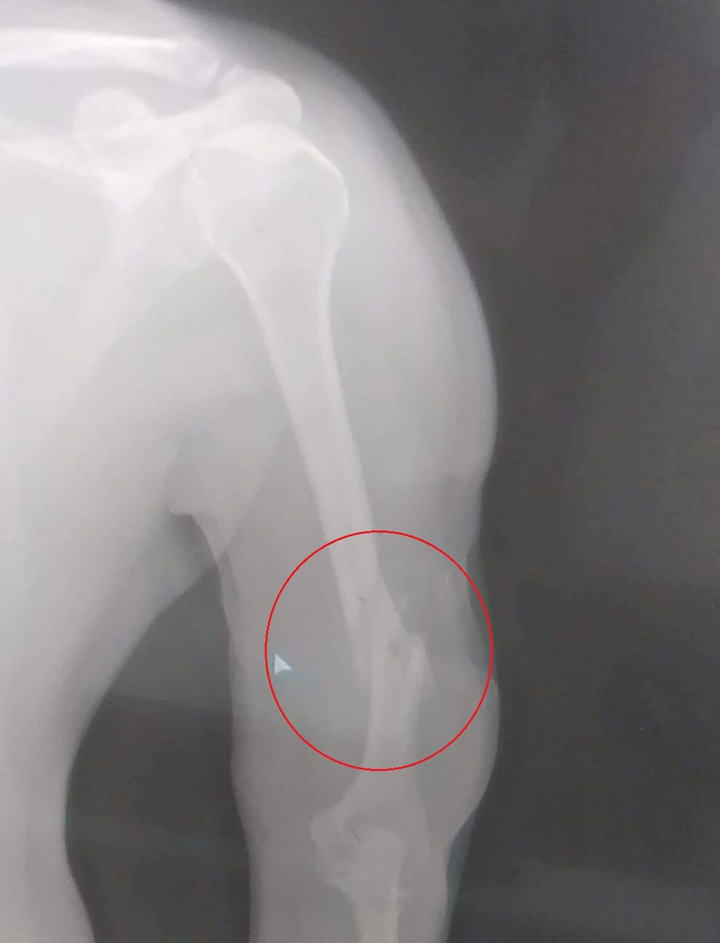

Sau đó, một kẻ đeo khẩu trang đi ô tô đến, cầm theo khẩu súng K59 lao vào quán bắn anh Nguyễn Đức T. hai phát đạn. Viên đạn thứ nhất bắn trượt, còn viên đạn thứ 2 trúng vào tay phải nạn nhân.

Anh Nguyễn Đức T. bị bắn gãy xương tay bên phải, không ảnh hưởng đến tính mạng.